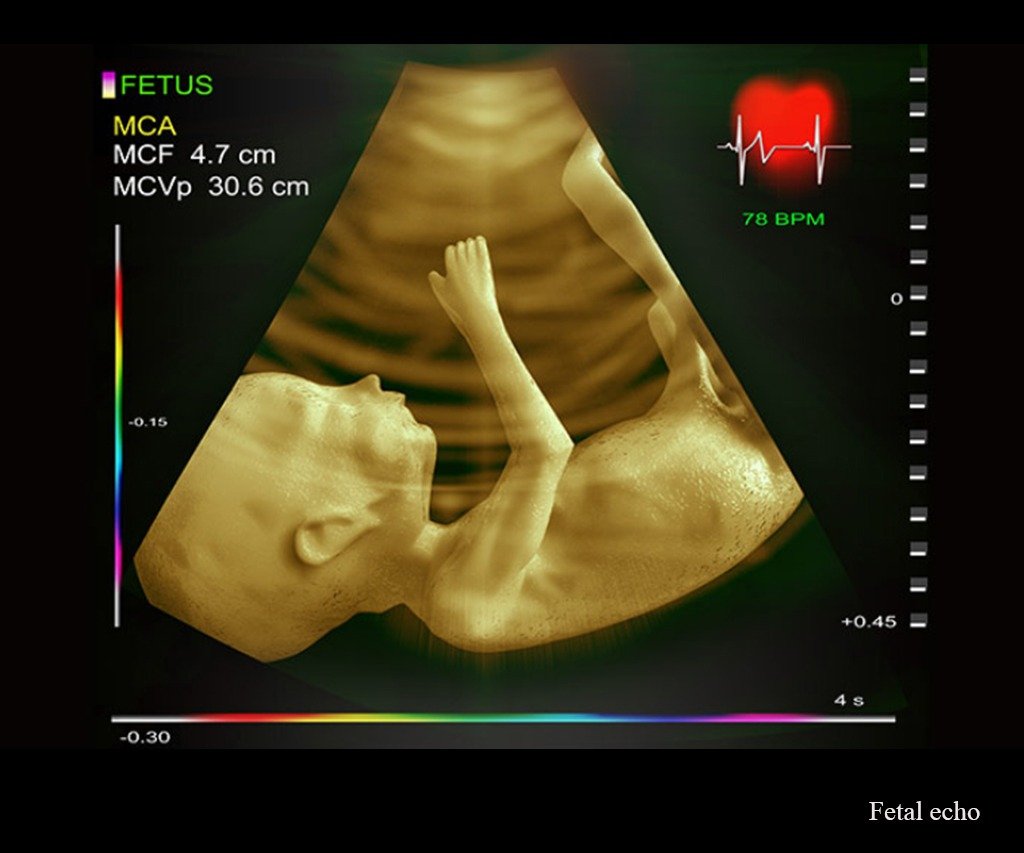

Fetal Cardiology/ Echocardiogram

Specialized pregnancy care focused on early detection and management of fetal conditions, ensuring the best possible outcomes for both mother and baby.

Fetal Services

Our Fetal Services department at Tiny Hearts offers comprehensive care for unborn babies diagnosed with medical conditions. We provide expertise in fetal medicine, fetal cardiology, and fetal interventions, ensuring early diagnosis and management of congenital anomalies before birth. Our specialized team works collaboratively to manage conditions such as congenital heart disease and genetic disorders, offering a full range of prenatal care and fetal interventions to improve outcomes for both mother and baby.